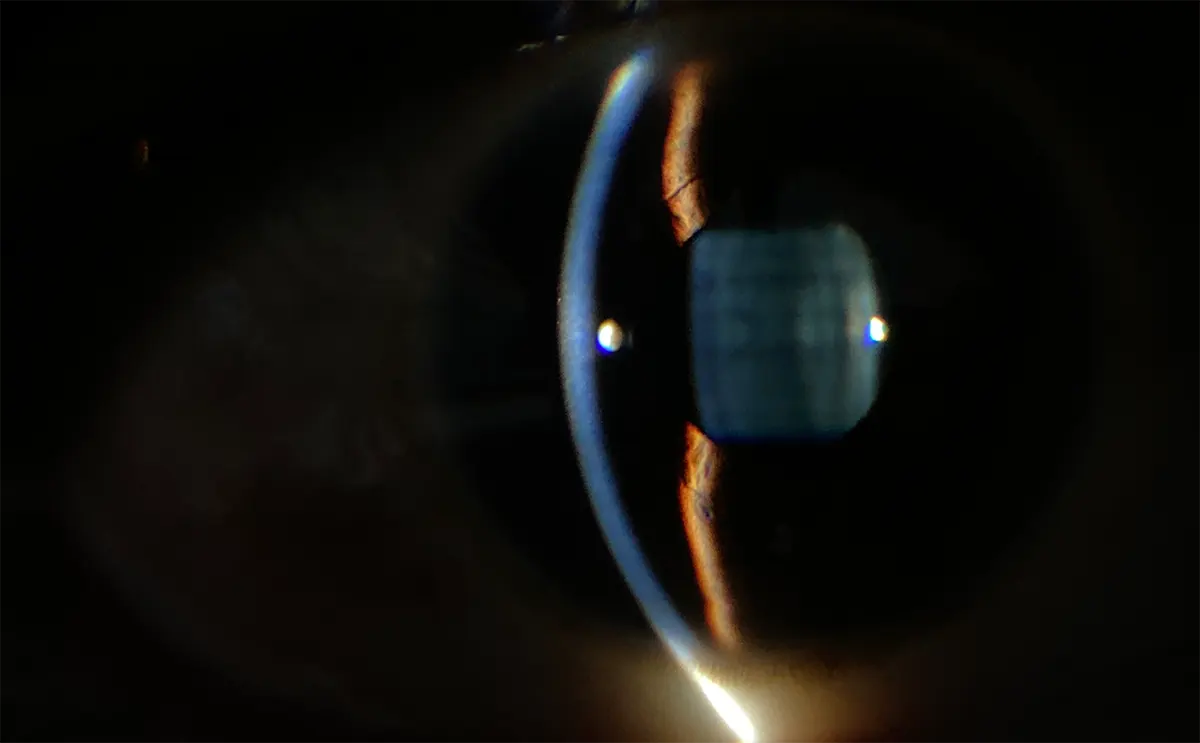

- Imágenes capturadas con la lámpara de hendidura portátil PSL-D20: Estas son imágenes de rendija y difusa capturadas con un PSL-D20. La luz difusa de múltiples colores y el control de intensidad facilitan la captura de imágenes de alta calidad.

Imágenes capturadas con PSL-D20

Estas son imágenes de rendija y difusa capturadas con un PSL-D20. La luz difusa de múltiples colores y el control de intensidad facilitan la captura de imágenes de alta calidad.